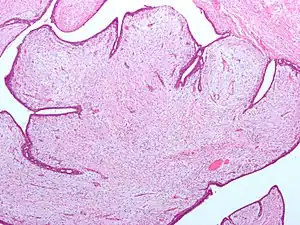

Tumor filoide (do Grego: phyllon folha), também conhecido como cistosarcoma filoide, é uma massa tipicamente grande, de crescimento rápido que se formam a partir das células estromais periductais da mama. Eles contribuem para menos de 1% de todas as neoplasias da mama.